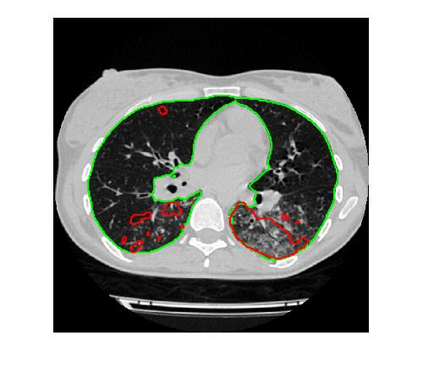

Since the breakout of coronavirus disease (COVID-19), the computer-aided diagnosis has become a necessity to prevent the spread of the virus. Detecting COVID-19 at an early stage is essential to reduce the mortality risk of the patients. In this study, a cascaded system is proposed to segment the lung, detect, localize, and quantify COVID-19 infections from computed tomography (CT) images Furthermore, the system classifies the severity of COVID-19 as mild, moderate, severe, or critical based on the percentage of infected lungs. An extensive set of experiments were performed using state-of-the-art deep Encoder-Decoder Convolutional Neural Networks (ED-CNNs), UNet, and Feature Pyramid Network (FPN), with different backbone (encoder) structures using the variants of DenseNet and ResNet. The conducted experiments showed the best performance for lung region segmentation with Dice Similarity Coefficient (DSC) of 97.19% and Intersection over Union (IoU) of 95.10% using U-Net model with the DenseNet 161 encoder. Furthermore, the proposed system achieved an elegant performance for COVID-19 infection segmentation with a DSC of 94.13% and IoU of 91.85% using the FPN model with the DenseNet201 encoder. The achieved performance is significantly superior to previous methods for COVID-19 lesion localization. Besides, the proposed system can reliably localize infection of various shapes and sizes, especially small infection regions, which are rarely considered in recent studies. Moreover, the proposed system achieved high COVID-19 detection performance with 99.64% sensitivity and 98.72% specificity. Finally, the system was able to discriminate between different severity levels of COVID-19 infection over a dataset of 1,110 subjects with sensitivity values of 98.3%, 71.2%, 77.8%, and 100% for mild, moderate, severe, and critical infections, respectively.